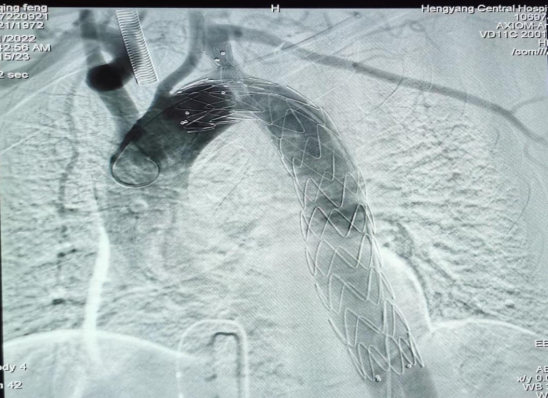

疾病的兇險與手術費的昂貴,讓許先生一家人左右為難。了解許先生經濟困難,心血管中心趙慶禧主任醫(yī)師與患者充分溝通后,決定放棄傳統的穿刺方法(需使用血管縫合器),行股動脈和左側肱動脈切開入路,既保證了手術安全性又兼顧了經濟性。最終在9月21日,許先生愿意接受介入微創(chuàng)治療。趙慶禧帶領介入團隊和麻醉科團隊密切配合,為其施行全麻下行“Castor分類型覆膜支架植入術”。僅在患者的左肱動脈,右股總動脈處分別做不到1cm的小切口,然后在DSA引導下精確定位,釋放覆膜支架一枚,保住鎖骨下動脈的同時也堵住了主動脈內膜破口,手術歷時三個小時,順利完成,“致命炸彈”被徹底拆除,術后許先生恢復良好,于住院的第30天順利出院。

(術中釋放的一體式覆膜支架)